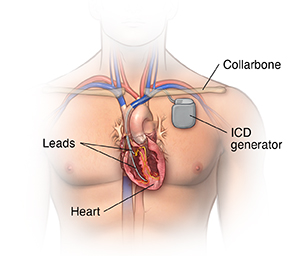

An implantable cardioverter defibrillator (ICD) looks similar to a pacemaker, though slightly larger. It works very much like a pacemaker. But the ICD can send an energy shock that resets an abnormal heartbeat back to normal.

Many devices combine a pacemaker and ICD in one unit for people who need both functions. After the shock is delivered, a "back-up" pacing mode is available if needed for a short while.

The ICD has another type of treatment for certain fast rhythms called anti-tachycardia pacing (ATP). This is a fast-pacing impulse sent to correct the rhythm. This can be used instead of shocking the heart in some cases.

Another type of ICD, called a subcutaneous ICD, does not involve placing a wire in the heart. Instead, this device is implanted in the left armpit (axillary) area. An ICD lead is tunneled under the skin over the sternum. It can deliver energy shocks to treat life-threatening heart rhythms. It can briefly act as a pacemaker if a normal heart rhythm is not restored.

A typical pacemaker or ICD has three main parts:

A pulse generator with a sealed lithium battery. It sends out the electrical signals that make the heart beat, or it sends out an electrical shock. Most generators can also receive and respond to signals sent by the heart itself.

One or more wires (leads). Leads are insulated flexible wires. They conduct electrical signals between the heart and the pulse generator. One end of the lead is attached to the pulse generator, and the electrode end of the lead is positioned in the heart. In the case of a biventricular pacemaker, leads are placed on both ventricles.

Electrodes. These are found on each lead.

Your doctor will make a small incision just under the collarbone. They will insert the pacemaker or ICD lead or leads into the heart through a blood vessel that runs under the collarbone. Once the lead is in place, your doctor can test it to make sure it is in the right place and is working. They then attach the lead to the generator (battery), which is placed just under the skin through the incision made earlier. Your doctor will close the incision with stitches, staples, or a medical glue (adhesive) and apply a dressing. Once the procedure has been completed, you will go through a recovery period of several hours.